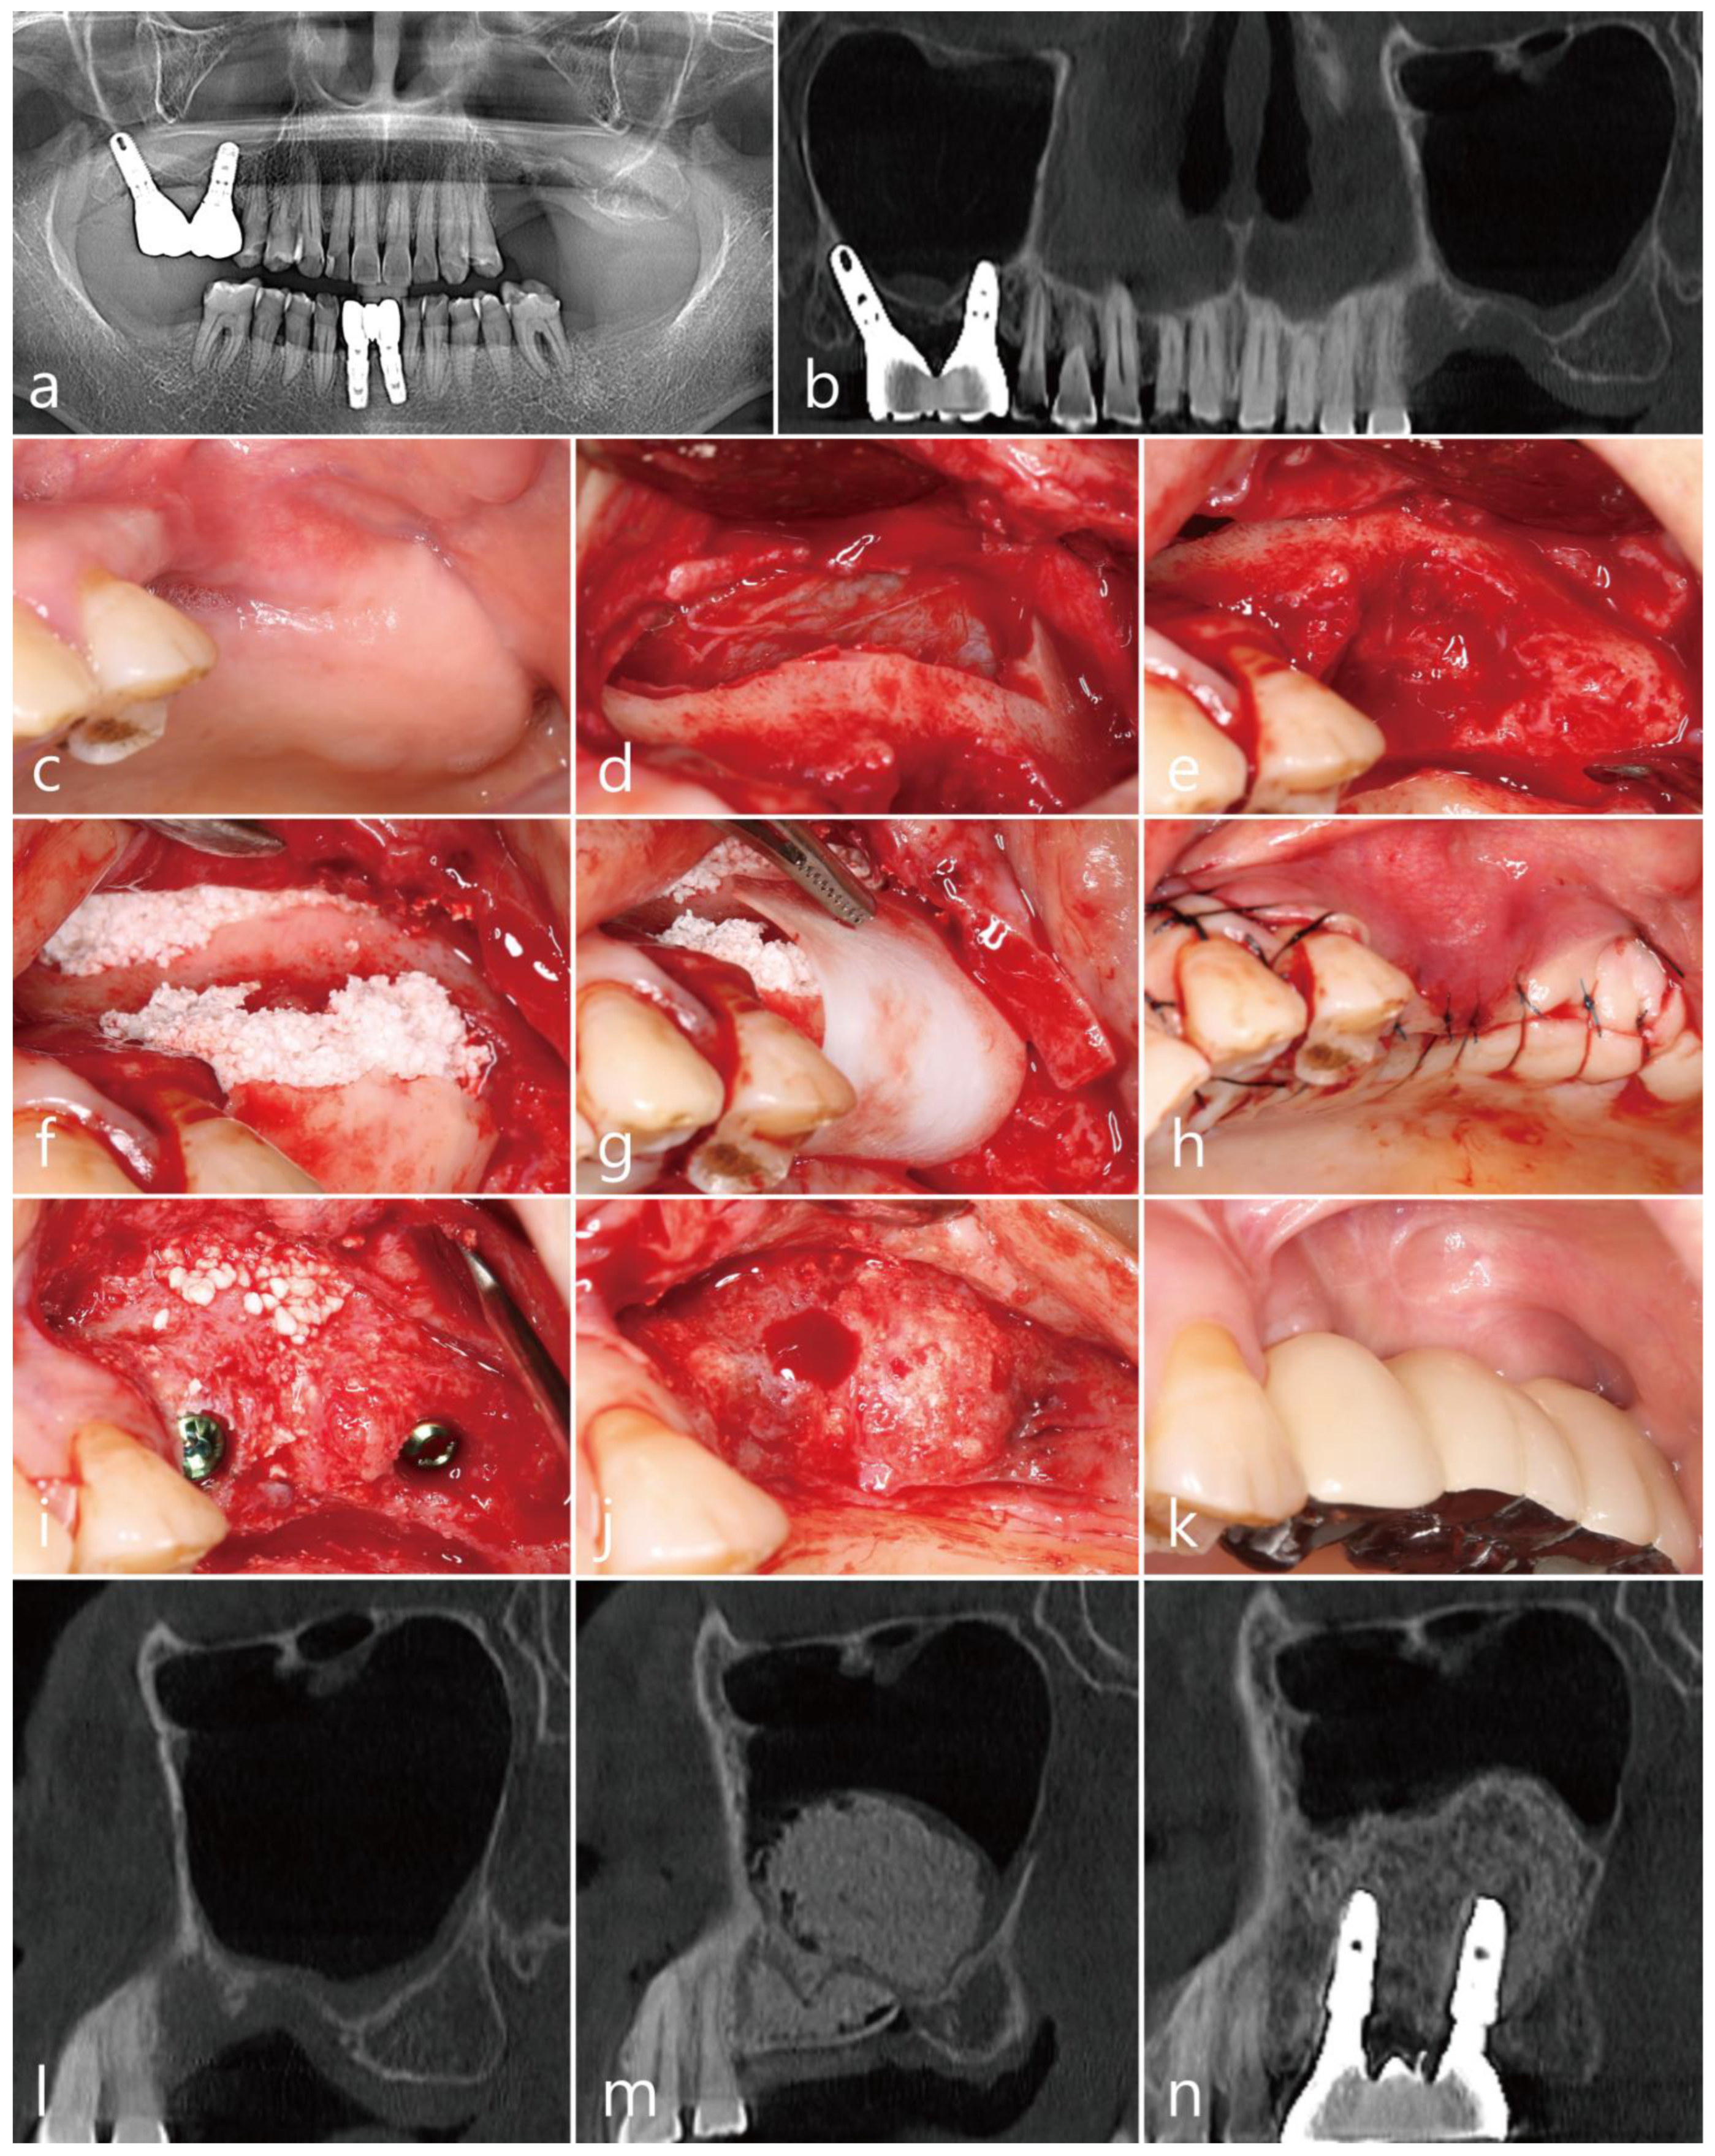

The patient was a 72 years old nonsmoking female, who visited the clinic for implant placement in the right posterior region of the maxilla (Table 1). She had undergone extractions of the maxillary right second premolar and second molar two months prior. The extraction site of the maxillary second molar exhibited severe vertical bone resorption. In addition, the right maxillary sinus was severely pneumatized (Figure 1a). The sagittal image of the preoperative cone-beam computed tomography (CBCT; RainbowTM CT, Dentium, Suwon, Republic of Korea; exposure time 10 s) scan revealed an intraosseous defect in the extraction site of the maxillary right second molar (Figure 1b). No posterior superior alveolar artery (PSAA) in the lateral sinus wall was observed in the CBCT scans (Table 1). A vertical deficiency of the soft tissue was also observed (Figure 1c). Lateral MSA and simultaneous implant placement were planned. The flaps were reflected under local anesthesia with 2% lidocaine (containing 1:100,000 epinephrine). After the removal of the granulation tissue in the extraction sites, MSA was performed using the lateral window technique with an Osteon II (Genoss Co., Ltd., Suwon, Republic of Korea), and the lateral sinus bony window was obtained. Two SLA-textured implants (Ø4.3 × 12 mm and Ø4.8 × 10 mm; Implantium, Dentium Co., Ltd., Suwon, Republic of Korea) were placed (Table 1, Figure 1d). The obtained lateral sinus bony window was passively placed without fixation to an intraosseous defect on the distal aspect of the implant placed in the right maxillary secondary molar site (Figure 1e). The surgical site was subsequently covered with a resorbable collagen membrane (Genoss Co., Ltd., Suwon, Republic of Korea) (Figure 1f), and the flaps were closed with 5-0 nylon sutures (Figure 1g). Antibiotics (ciprofloxacin 500 mg; Ildong Pharmaceutical Co., Ltd., Seoul, Republic of Korea) and a nonsteroidal anti-inflammatory drug (Etodol; 200 mg; Yuhan Co., Ltd., Seoul, Republic of Korea) were prescribed for 10 days. The sutures were removed after two weeks. Transient post-operative swelling and pain were reported, but healing was uneventful. The uncovering procedure was performed six months after the surgery (Figure 1h). A prosthesis was delivered two months after the uncovering procedure. Two years after prosthesis delivery, no abnormal findings were observed around the implant (Figure 1i). The sagittal view of the CBCT scan performed immediately after surgery shows a well-placed lateral window bone in the distal defect of the implant placed in the maxillary right second molar site (Figure 1j). In the sagittal image of the CBCT scan performed immediately after the prosthesis delivery, the lateral sinus window bone was well incorporated with the surrounding native bone (Figure 1k). The sagittal CBCT scans two years after the prosthesis delivery revealed an improved bony density (Figure 1l).

Figure 1. Case 1: (a) preoperative panoramic radiograph; (b) sagittal image of the preoperative CBCT scan showing a severely resorbed bone defect; (c) preoperative clinical view two months after tooth extraction; (d) after the flap reflection, a lateral window was prepared, and the buccal bony window was obtained during the maxillary sinus augmentation; (e) the obtained lateral bony window was passively placed on the distal intraosseous defect of the #17 implant without fixation; (f) the surgical site was covered with a resorbable collagen membrane; (g) the flaps were closed with minimal tension; (h) the uncovering procedure was performed six months after the operation, and the lateral window bone was well incorporated with the adjacent native bone; (i) clinical view at two years after prosthesis delivery; (j) panoramic radiograph immediately after surgery; (k) sagittal image of the CBCT scans after prosthesis delivery; (l) sagittal image of the CBCT two years after prosthesis delivery, where the lateral bony window was well incorporated with the surrounding native bone, and the bone density was increased.